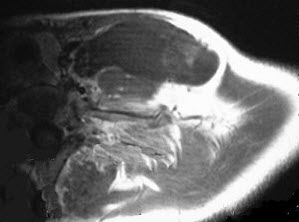

37岁女性,左侧颈部肿块渐进性增大,无压痛,局部皮温不高,CT、MRI扫描如图所示,请选择正确的描述或诊断()。

A、CT发现左侧颈后三角区可见低密度肿块影

B、增强扫描未见强化

C、MRI的T

1

WI呈低信号

D、MRI的T

2

WI呈高信号,其内可见分隔

E、考虑为淋巴管囊肿

A,B,C,D,E